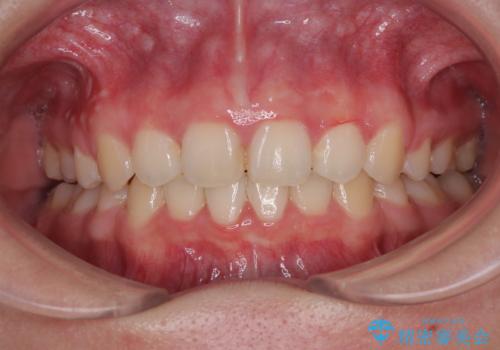

銀歯の下に虫歯 〈オールセラミッククラウン〉

担当医 瀧村怜未